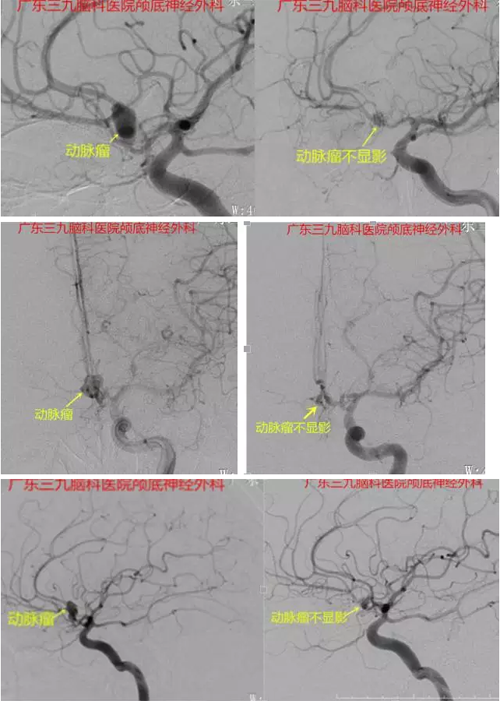

图3、4、5:术前术后DSA对比,箭头所示动脉瘤,术后动脉瘤夹形态稳定,动脉通畅

前交通动脉是颅内动脉瘤的高发部位,易破裂出血,其出血后致死致残率极高,早期显微手术可提高手术安全性,规避脑动脉瘤再次破裂,使致死率及致残率下降,改善患者预后。但因前交通动脉瘤位置深在,毗邻下丘脑、视交叉、垂体柄等重要结构,血管多且功能重要,动脉瘤方向多变,故手术要求高,手术难度大,术后可能出现发热、认知障碍,严重者可出现偏瘫、昏迷等。本例术前行CTA及DSA检查且结果吻合,提示前交通动脉示一较大不规则囊状突起,范围约9.7mm×9.3mm,瘤颈宽3mm。完善检查后早期行动脉瘤夹闭,术程顺利,术中尽量减少出血,阻断后予迅速夹闭,准确有效,减少缺血时间,术后患者恢复良好,术后复查DSA提示动脉瘤夹形态稳定,前交通动脉通畅。